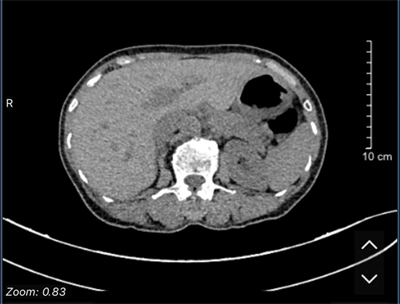

UNG THƯ BIỂU MÔ TẾ BÀO THẬN

Ung thư thận là loại ung thư thường gặp đứng thứ 14 trên toàn cầu, với hơn 430.000 ca mới được chẩn đoán vào năm 2020, và 434840 ca mắc trên toàn cầu vào năm 2022. Tỷ lệ mắc thay đổi theo khu vực địa lý, cao hơn ở châu Âu và Bắc Mỹ. Ung...